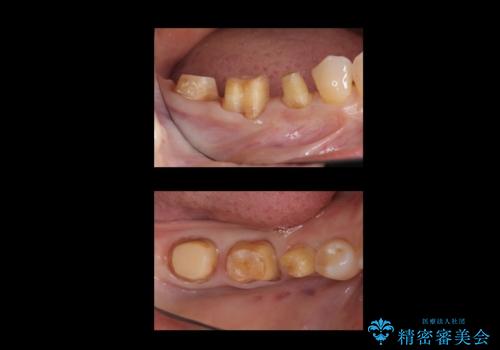

左上は他院でインプラントを入れたが、クラウンの脱離を繰り返して、仮歯に戻したあともうそれでいいと言われたとのことでした。

仮歯はすっかり劣化、変質しており、上記の写真のように隣の歯が虫歯になっている状態でした。

インプラントの製造会社は当院で使っているものと異なったため、ドライバー等購入し対応しました。